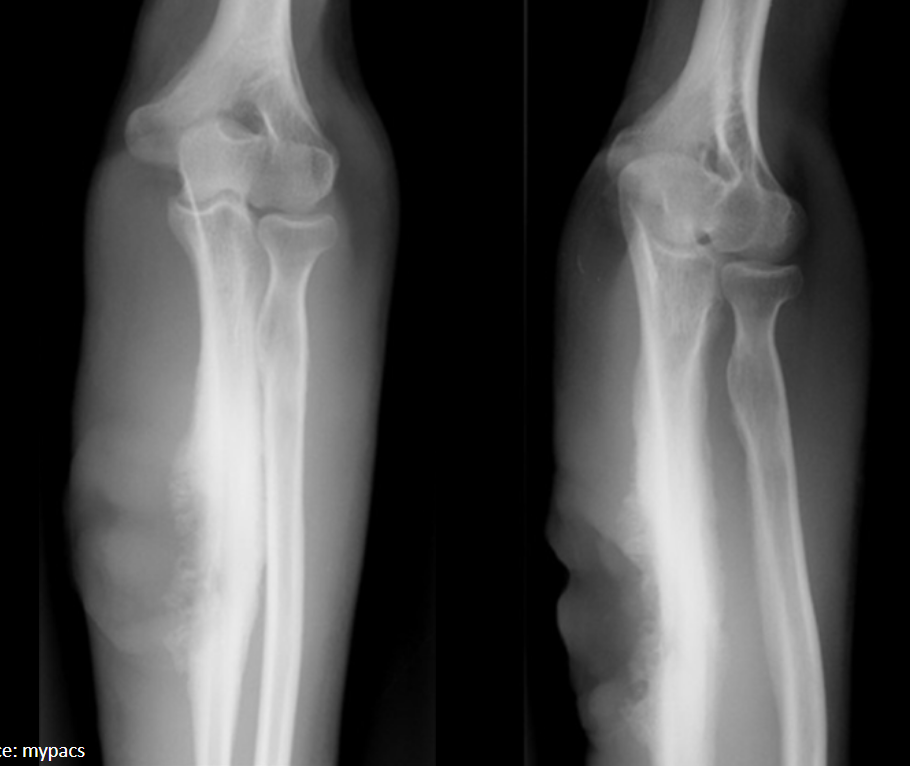

Laminated periosteal reaction (aggressive)

1. Osteomyelitis

2. Ewing sarcoma

3. Osteosarcoma

4. Lymphoma

diaphyseal lesion in immature skeleton

What pattern of destruction is present?

What are the top three differential diagnoses?

A

Permeative lytic (aggressive)

2. Ewing sarcoma (diaphysis)

3. Osteosarcoma (metaphysis)

immature skeleton